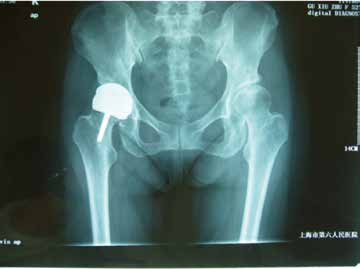

作为年轻患者高功能活动需求,髋关节表面置换术的出现具有重要意义,这么说并不意味髋关节表面置换术结果一定好,没有手术风险,什么人都可以做。表面置换的优点并非自然和良好的功能和临床结果划等号,表面置换的长期临床结果还缺乏人工全髋关节置换那样大量循证医学证据证实。手术者必需经过严格的专门培训,具有大量临床全髋关节置换术的经验,并规范地使用这一技术操作;同时,对患者的选择和手术指征的把握亦同等重要。虽然,髋关节骨关节炎、股骨头坏死、髋关节发育不良、强直性脊柱炎等均可以行表面置换术,但手术指征需严格把握,切忌将严重的股骨头坏死、僵直的强直性脊柱炎患者、Crowe Ⅲ和Crowe Ⅳ型髋关节发育不良的患者进行表面置换术。尤其对刚开始应用这一技术的医师,你可以很艰苦地把手术做下来并提供一张看似不错的X线片,但这并不意味这些患者具有合适的手术指征;此外由于国人多数体格较小,髋关节解剖结构不同于西方人,应避免选择颈干角小于130°、颈长低于3cm,头颈比例小于1.3:1的患者。

图1:A和B:髋关节表面置换使得年轻患者髋关节的骨量得到最大限度的保留。C:术后X线片显示患者髋关节的生物力学参数得到良好的重建。D:由于大直径的假体设计为患者提供了可靠的稳定性,患者获得了满意的髋关节功能及活动度。